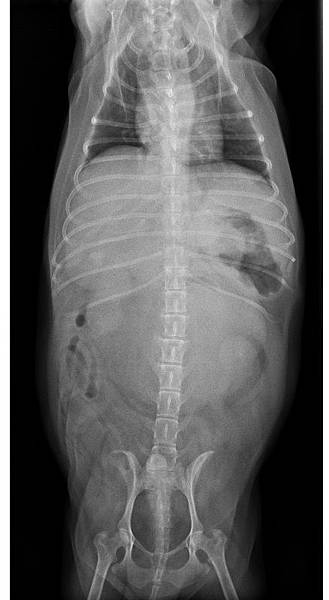

手術後X光

未命名2.jpg